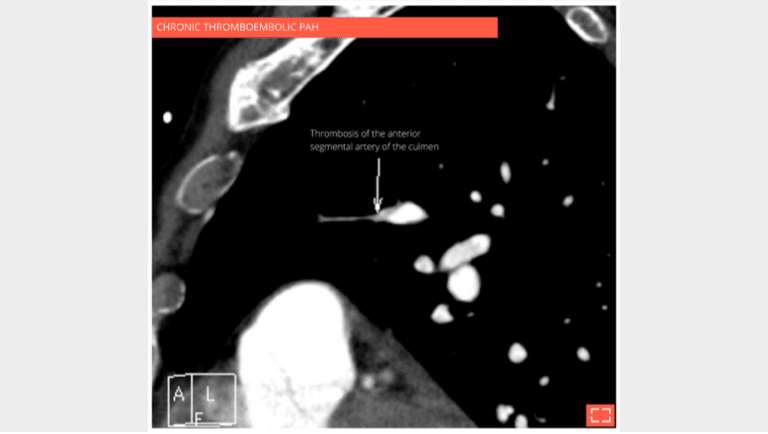

The CT scan with contrast medium injection to check for pulmonary artery obstruction shows the small size and distal thrombosis of peripheral pulmonary arteries, confirming chronic thrombosis. Ventilation-perfusion scintigraphy is the recommended exam for screening for these anomalies.